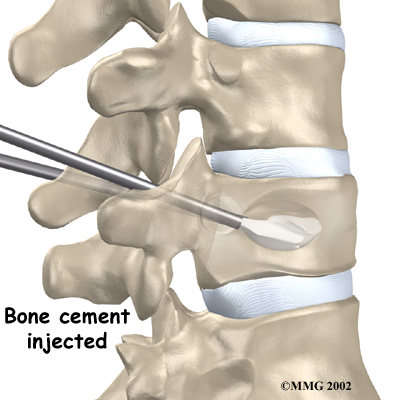

Next, the surgeon removes the balloon and injects bone cement into the hollow space formed by the balloon. A chemical reaction in the cement causes it to harden in about 15 minutes. This fixes the bone in its corrected height and position. Bandages are then applied over the small incisions.

Injecting Bone Cement